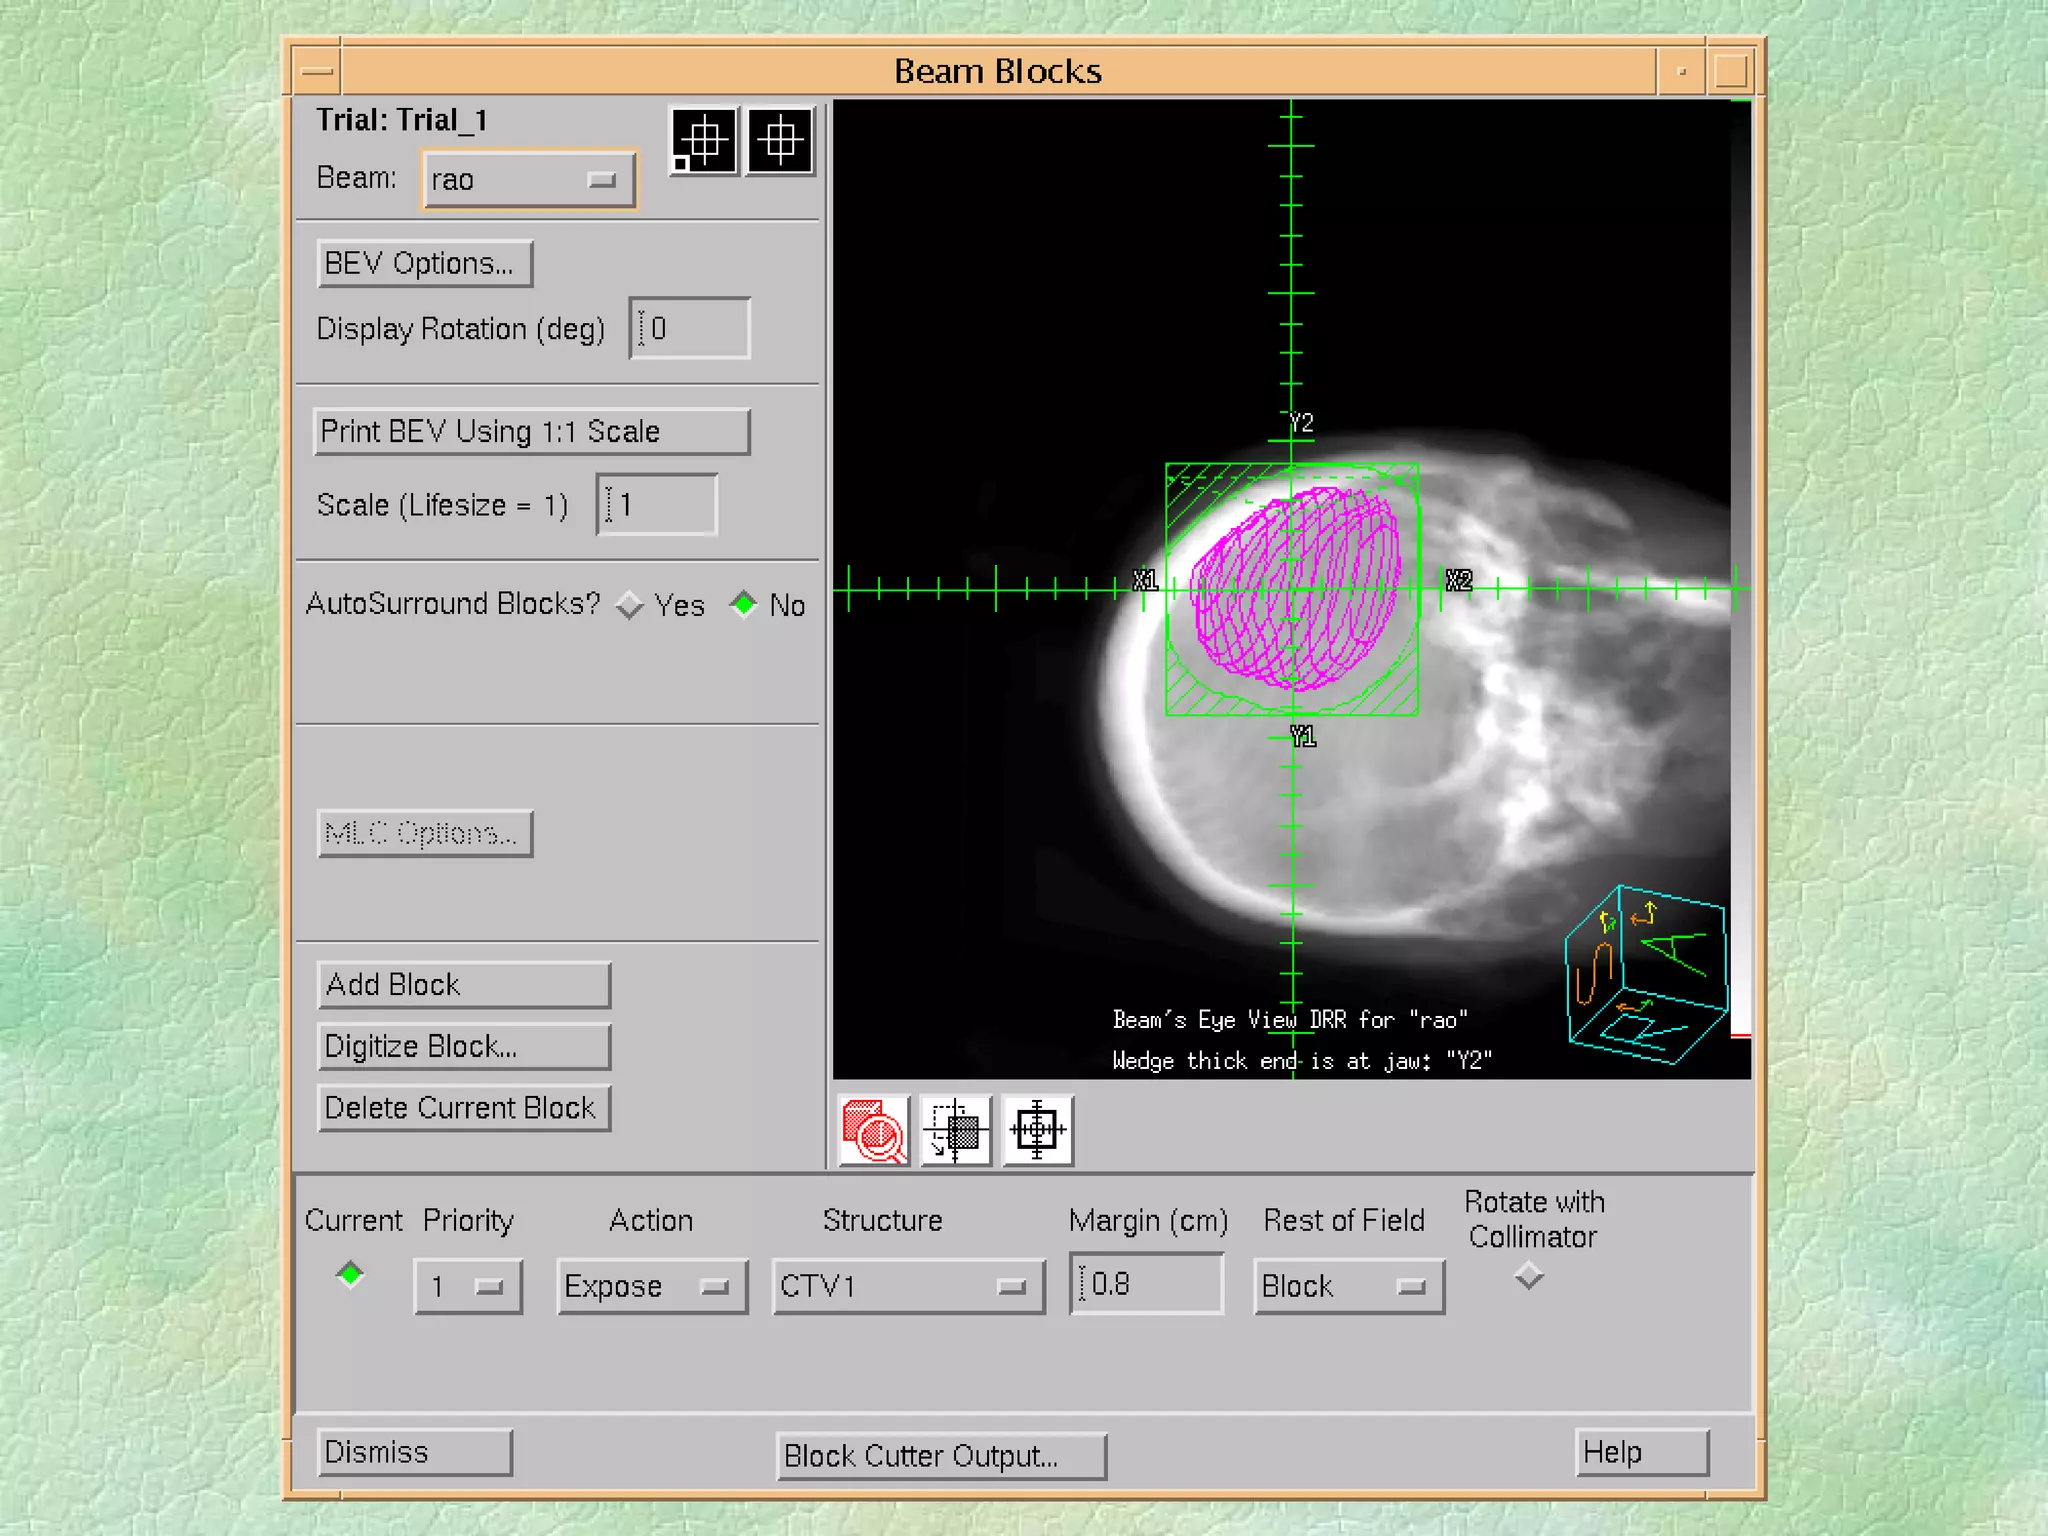

Virtual Simulation: -  Immobilization CT Coordinate system Structure Delineation Isocentre localization Beam placement/definition

Problems: Images arestatic and organ motion is not evident Correlation of imager/patient/treatment coordinate systems is non-trivial - DRRs Resolution of data set is limited by slice thickness - structure definition/DRR Imaging modality - image fusion

Problems: Images are static and organ motion is not evident Correlation of imager/patient/treatment coordinate systems is non-trivial - DRRs Resolution of data set is limited by slice thickness - structure definition/DRR Imaging modality - image fusion